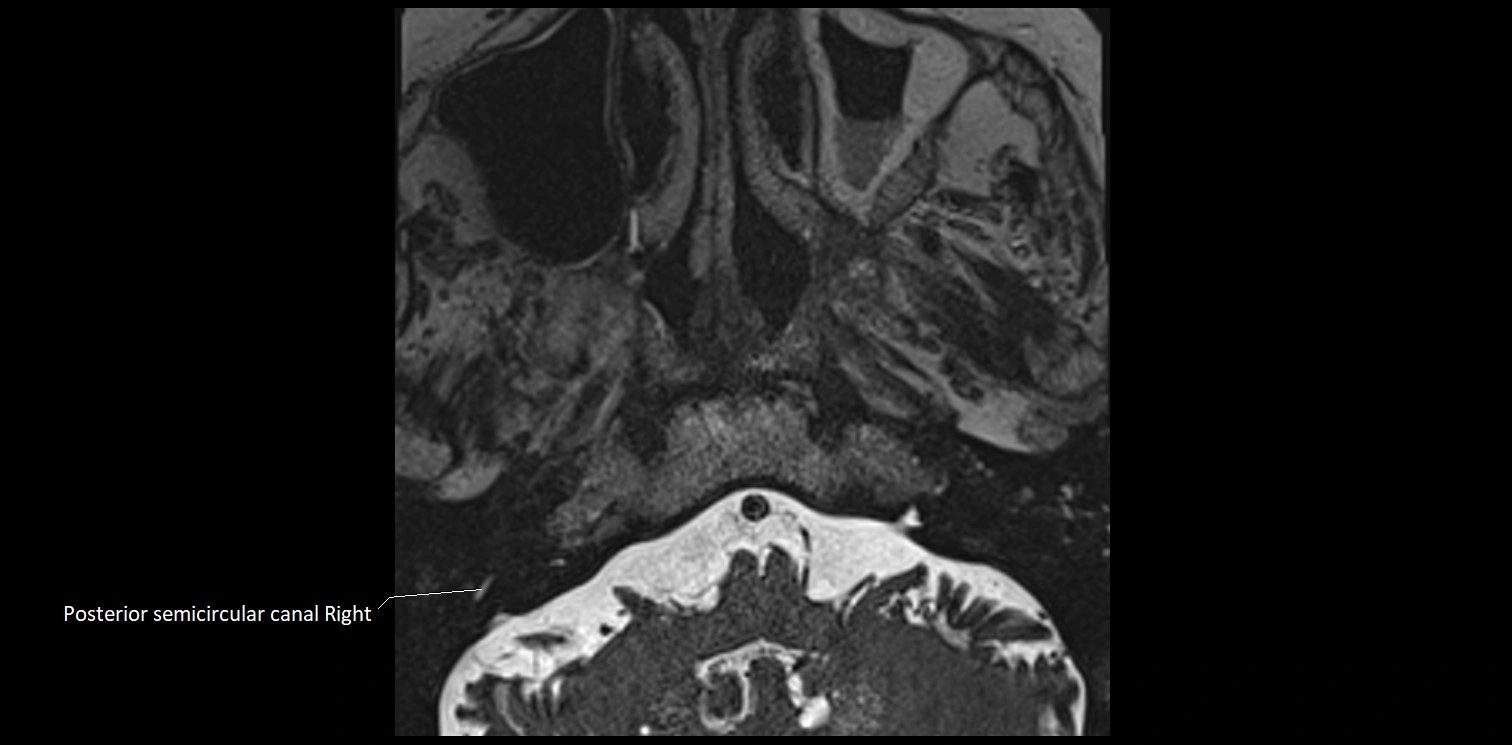

MRI images

image